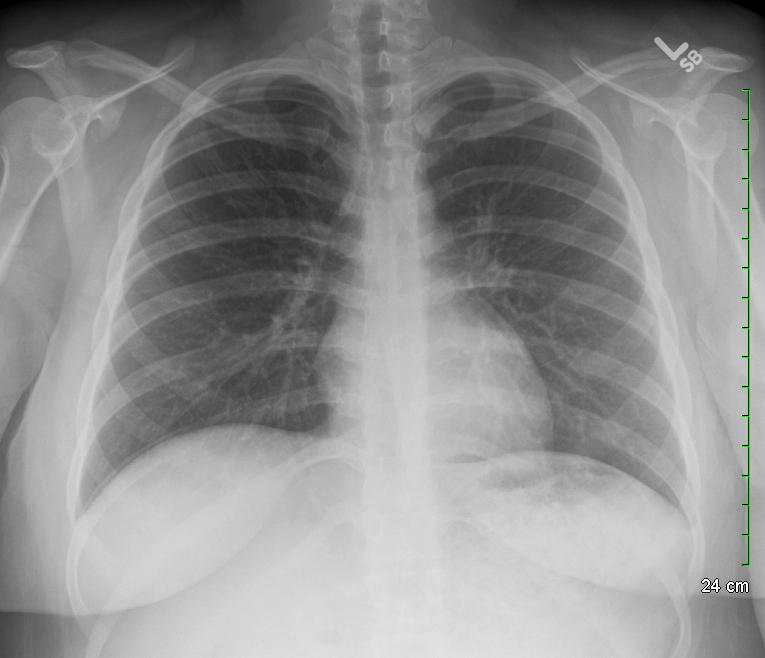

OVERVIEW

This page provides an archive for various chest X-rays that were all read as “unremarkable” (i.e. normal). This page will serve as a reference point for observing remarkable/abnormal findings in patients who have pathology that can be appreciated on a chest X-ray. This page is meant to be used in combination with the page that covers how to interpret a chest X-ray.

POSTERIOR-ANTERIOR (PA) VIEW

A very common (and one of the preferred views) for a chest X-ray is the PA view. Here are all examples of normal chest X-rays obtained with this view. CLICK ON THE THUMBNAILS BELOW TO OPEN UP THE ARCHIVE